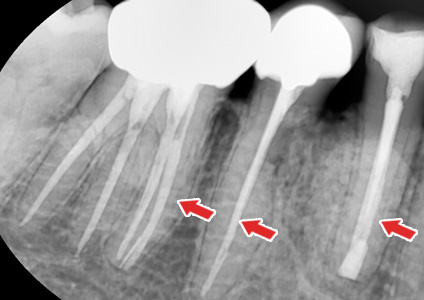

½Å°æÄ¡·á 2.

½Å°æÄ¡·á¸¦ ÇÑ Ä¡¾ÆÀÇ X-ray »çÁø